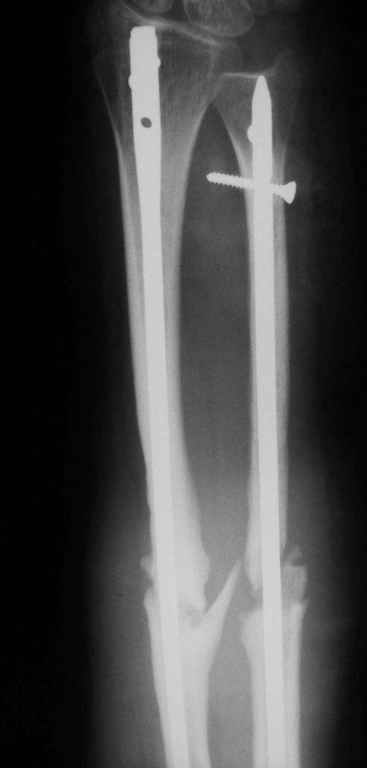

Уважаемые коллеги! У нас в травматологическом отделении клиник кафедры травматологии Самарского медуниверситета находится пациентка с ложными суставами костей предплечья, после остеосинтеза спицами (8 месяцев).

Девушка молодая, аппарат внешней фиксации категорически не приемлет. Выполнен закрытый БИОС СнМ с расверливанием (сверлом 4,5 мм). Хотелось ознакомиться с вашими комментариями.